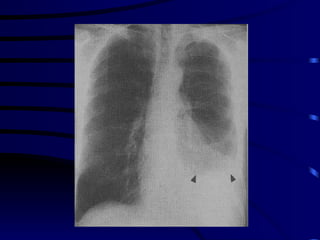

Additional Clinical Adverse Prognostic Features PO 2 <60 mm or O 2  saturation < 90 % Bilateral or multilobar (>2 lobes) infiltrates on chest radiograph

SEVERE CAP There is no universally accepted definition of severe CAP: 1. Respiratory frequency >30 breaths min at admission 2. Severe respiratory failure defined by a Pao2/Flo2 ratio <250  3. Requirement for mechanical ventilation 4. Chest radiograph showing    a) bilateral involvement    b) involvement of multiple lobes   c) an    in the size of the opacity by   50 % within 48 h of  admission  5. Shock ( SBP < 90 mmHg or DBP < 60 mmHg)  6. Requirement for vasopressors for more than 4 h 7. Urine output < 20 ml/h or acute renal failure requiring dialysis

Decision to Hospitalize 4. Laboratory findings   a. WBC <4,000/mcL or >30,000/mcL  b. Pao2 <60 mmHg or Paco2 of >50 mmHg on room air.  c. Need for mechanical ventilation.  d. Serum creatinine >1.2 mg/dl or BUN >20 mg/dl (>7 mmol/L) e. Unfavorable chest radiographic findings: -  more than one lobe involvement -  presence of a cavity -  rapid radiographic spread  - pleural effusion  f.  Hct of <30 %  or hemoglobin <9 g/dl g. Evidence of sepsis or organ dysfunction as manifested by a metabolic acidosis, an increased PT, an increased PTT,  decreased platelets,  fibrin split products > 1:40

SOME FACTS ABOUT CAP The  etiologic agent  causing CAP cannot be accurately predicted from clinical or radiological features The term ‘ atypical pneumonia ’ should be abandoned Elderly patients  with CAP more frequently present with non specific symptoms and are less likely to have fever Radiological resolution  lags behind clinical improvement  Radiological resolution  is slow in the elderly and cases of multilobar involvement.